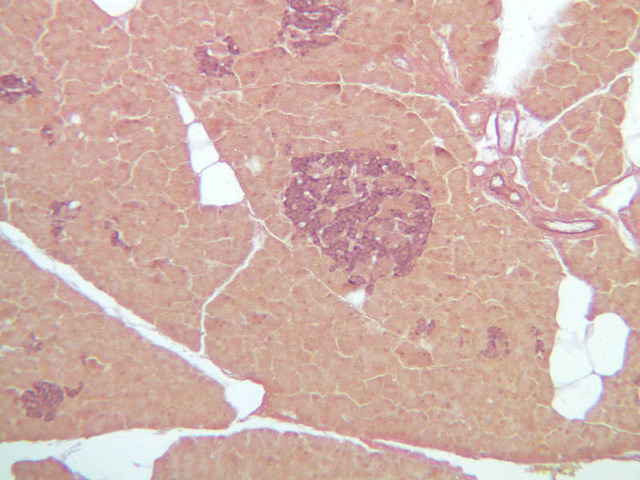

Study the distribution of glycogen in the sections of liver stained by the PAS method on slides B-31 ([2.5x-labeled, 10x, 20x, 40x] [2.5x, 10x, 20x, 40x-labeled]) and B-34 ([2.5x, 10x, 20x, 40x]. The tissue on slide B-34 was taken from an animal treated with glucagon. Had the specimens on slides B-31 and B-34 been prepared in a carefully controlled way, what difference would you expect to see in their glycogen deposits?